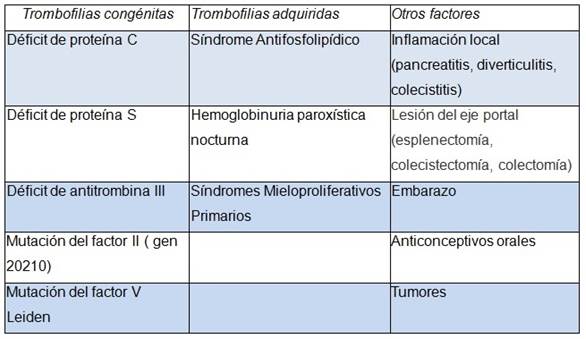

Luego de diagnosticada la colangiopatía portal, es imprescindible el estudio de la causa de la trombosis, por lo que se estudiaron los factores protrombóticos hereditarios y adquiridos. Los neoplasmas mieloproliferativos son la causa más frecuente de trombosis portal en adultos y en este caso se detectó la presencia de la mutación V617 del gen JAK2 apoyando el diagnóstico de Trombocitosis Esencial, sin encontrar otros factores coadyuvantes. En la mayoría de los casos la trombosis portal es de etiología multifactorial y en la Tabla 2 se resumen las etiologías más frecuentes. Es importante tener presente que como consecuencia del hiperesplenismo y la hemodilución, el recuento de células sanguíneas frecuentemente es normal. El recuento plaquetario por encima de 200 mil en un paciente con esplenomegalia e hipertensión portal, lleva a la sospecha de un síndrome mieloproliferativo como es el caso de la paciente que se detalla. Se inició anticoagulación previa ligadura endoscópica de las várices esofágicas. En la evolución se mantuvo asintomática y se constató normalización del hepatograma sin mediar tratamiento específico.